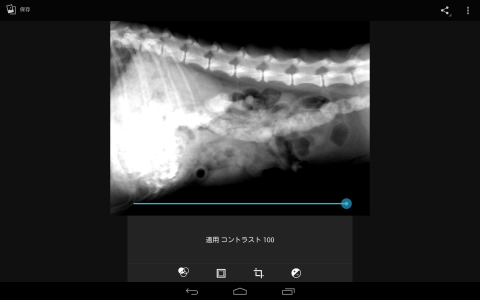

しかし、デフォルトで入っているビューアーでも簡易的な画像処理がかけられるので、使ってみました。

明るさ補正で若干暗くしたものになります。これでも余分な軟部組織がとんで、骨や内蔵がはっきり見られるようになります。

またコントラストを調整すると

黒いところはより黒く、白いところはより白くと画像に強弱が付くようになります。明るさ補正で処理をしたものよりも、さらに骨や内蔵の形態がはっきりと描画されるようになります。

明るさや、コントラストを調整することにより、今まで生のレントゲンでははっきりしなかった、臓器がかぶっている画像を強調して描出できるようになります。